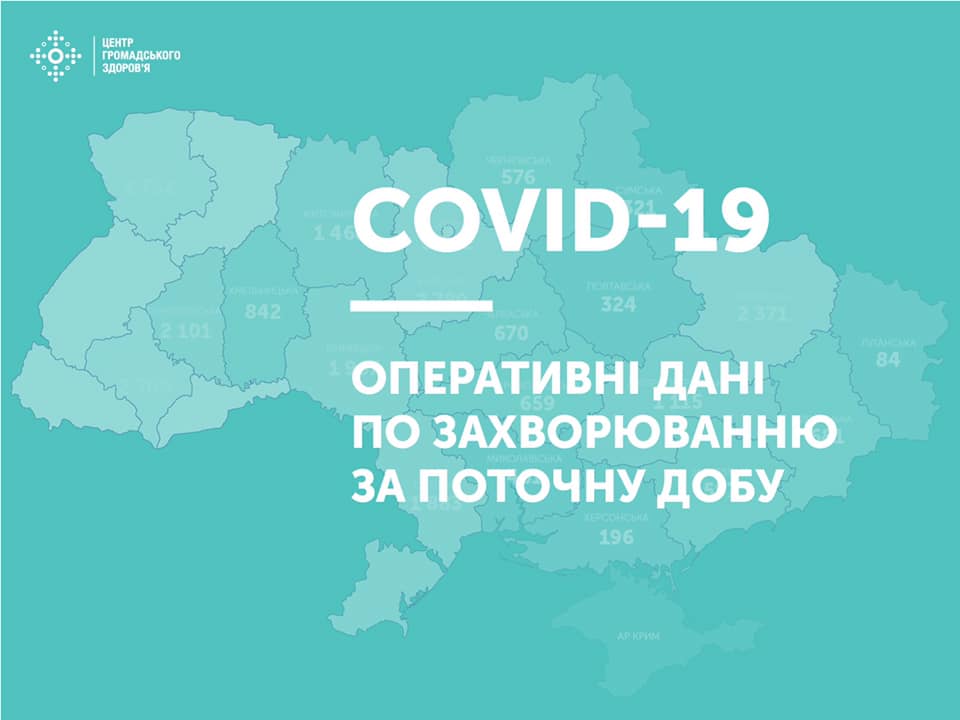

Більше 3 тисяч випадків захворювання на коронавірус зафіксували в Україні за добу

11.09.2020 09:37